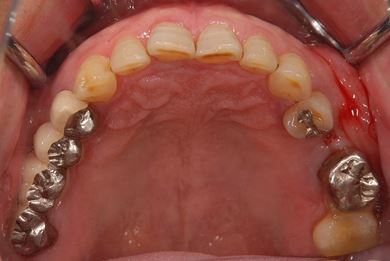

インプラントの症例写真 IMPLANT

抜歯即日スピードインプラント治療

| 治療内容 | インプラント2本(抜歯即日スピードインプラント) | ||||||||||||||||||||||||||||||||